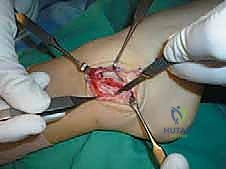

الخطوة السابعة: تعديل جولد (The Gould Modification) - سر القوة الإضافية

لضمان عدم تكرار التمزق، خاصة للرياضيين، يضيف الجراح خطوة "تعديل جولد". تتمثل هذه الخطوة في سحب جزء من النسيج الليفي القوي المجاور والمسمى بـ "القيد الباسط السفلي" (Inferior Extensor Retinaculum) وخياطته فوق الأربطة التي تم إصلاحها. يعمل هذا النسيج كـ "حزام أمان" إضاف

يتم تمرير الخيوط الجراحية القوية عبر الأربطة الممزقة (ATFL و CFL) والكبسولة المفصلية. أثناء عقد هذه الخيوط، يتم وضع الكاحل في وضعية الانقلاب الخارجي (Eversion) والانعطاف الظهري (Dorsiflexion) لضمان شد الأربطة بأقصى درجة ممكنة، مما يعيد للكاحل ثباته الفوري.